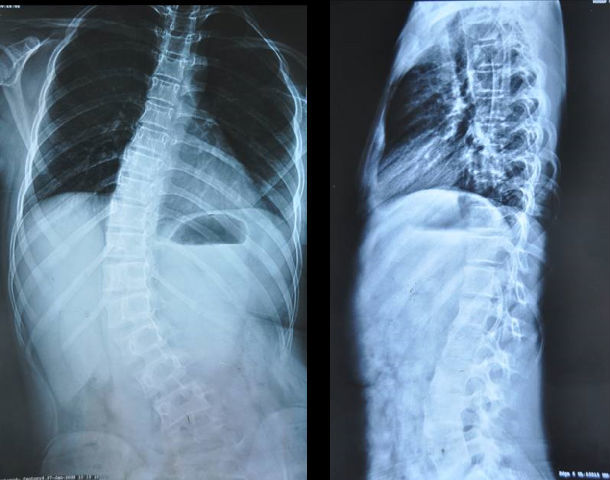

脊柱侧弯专科典型病例四

图片尺寸432x600